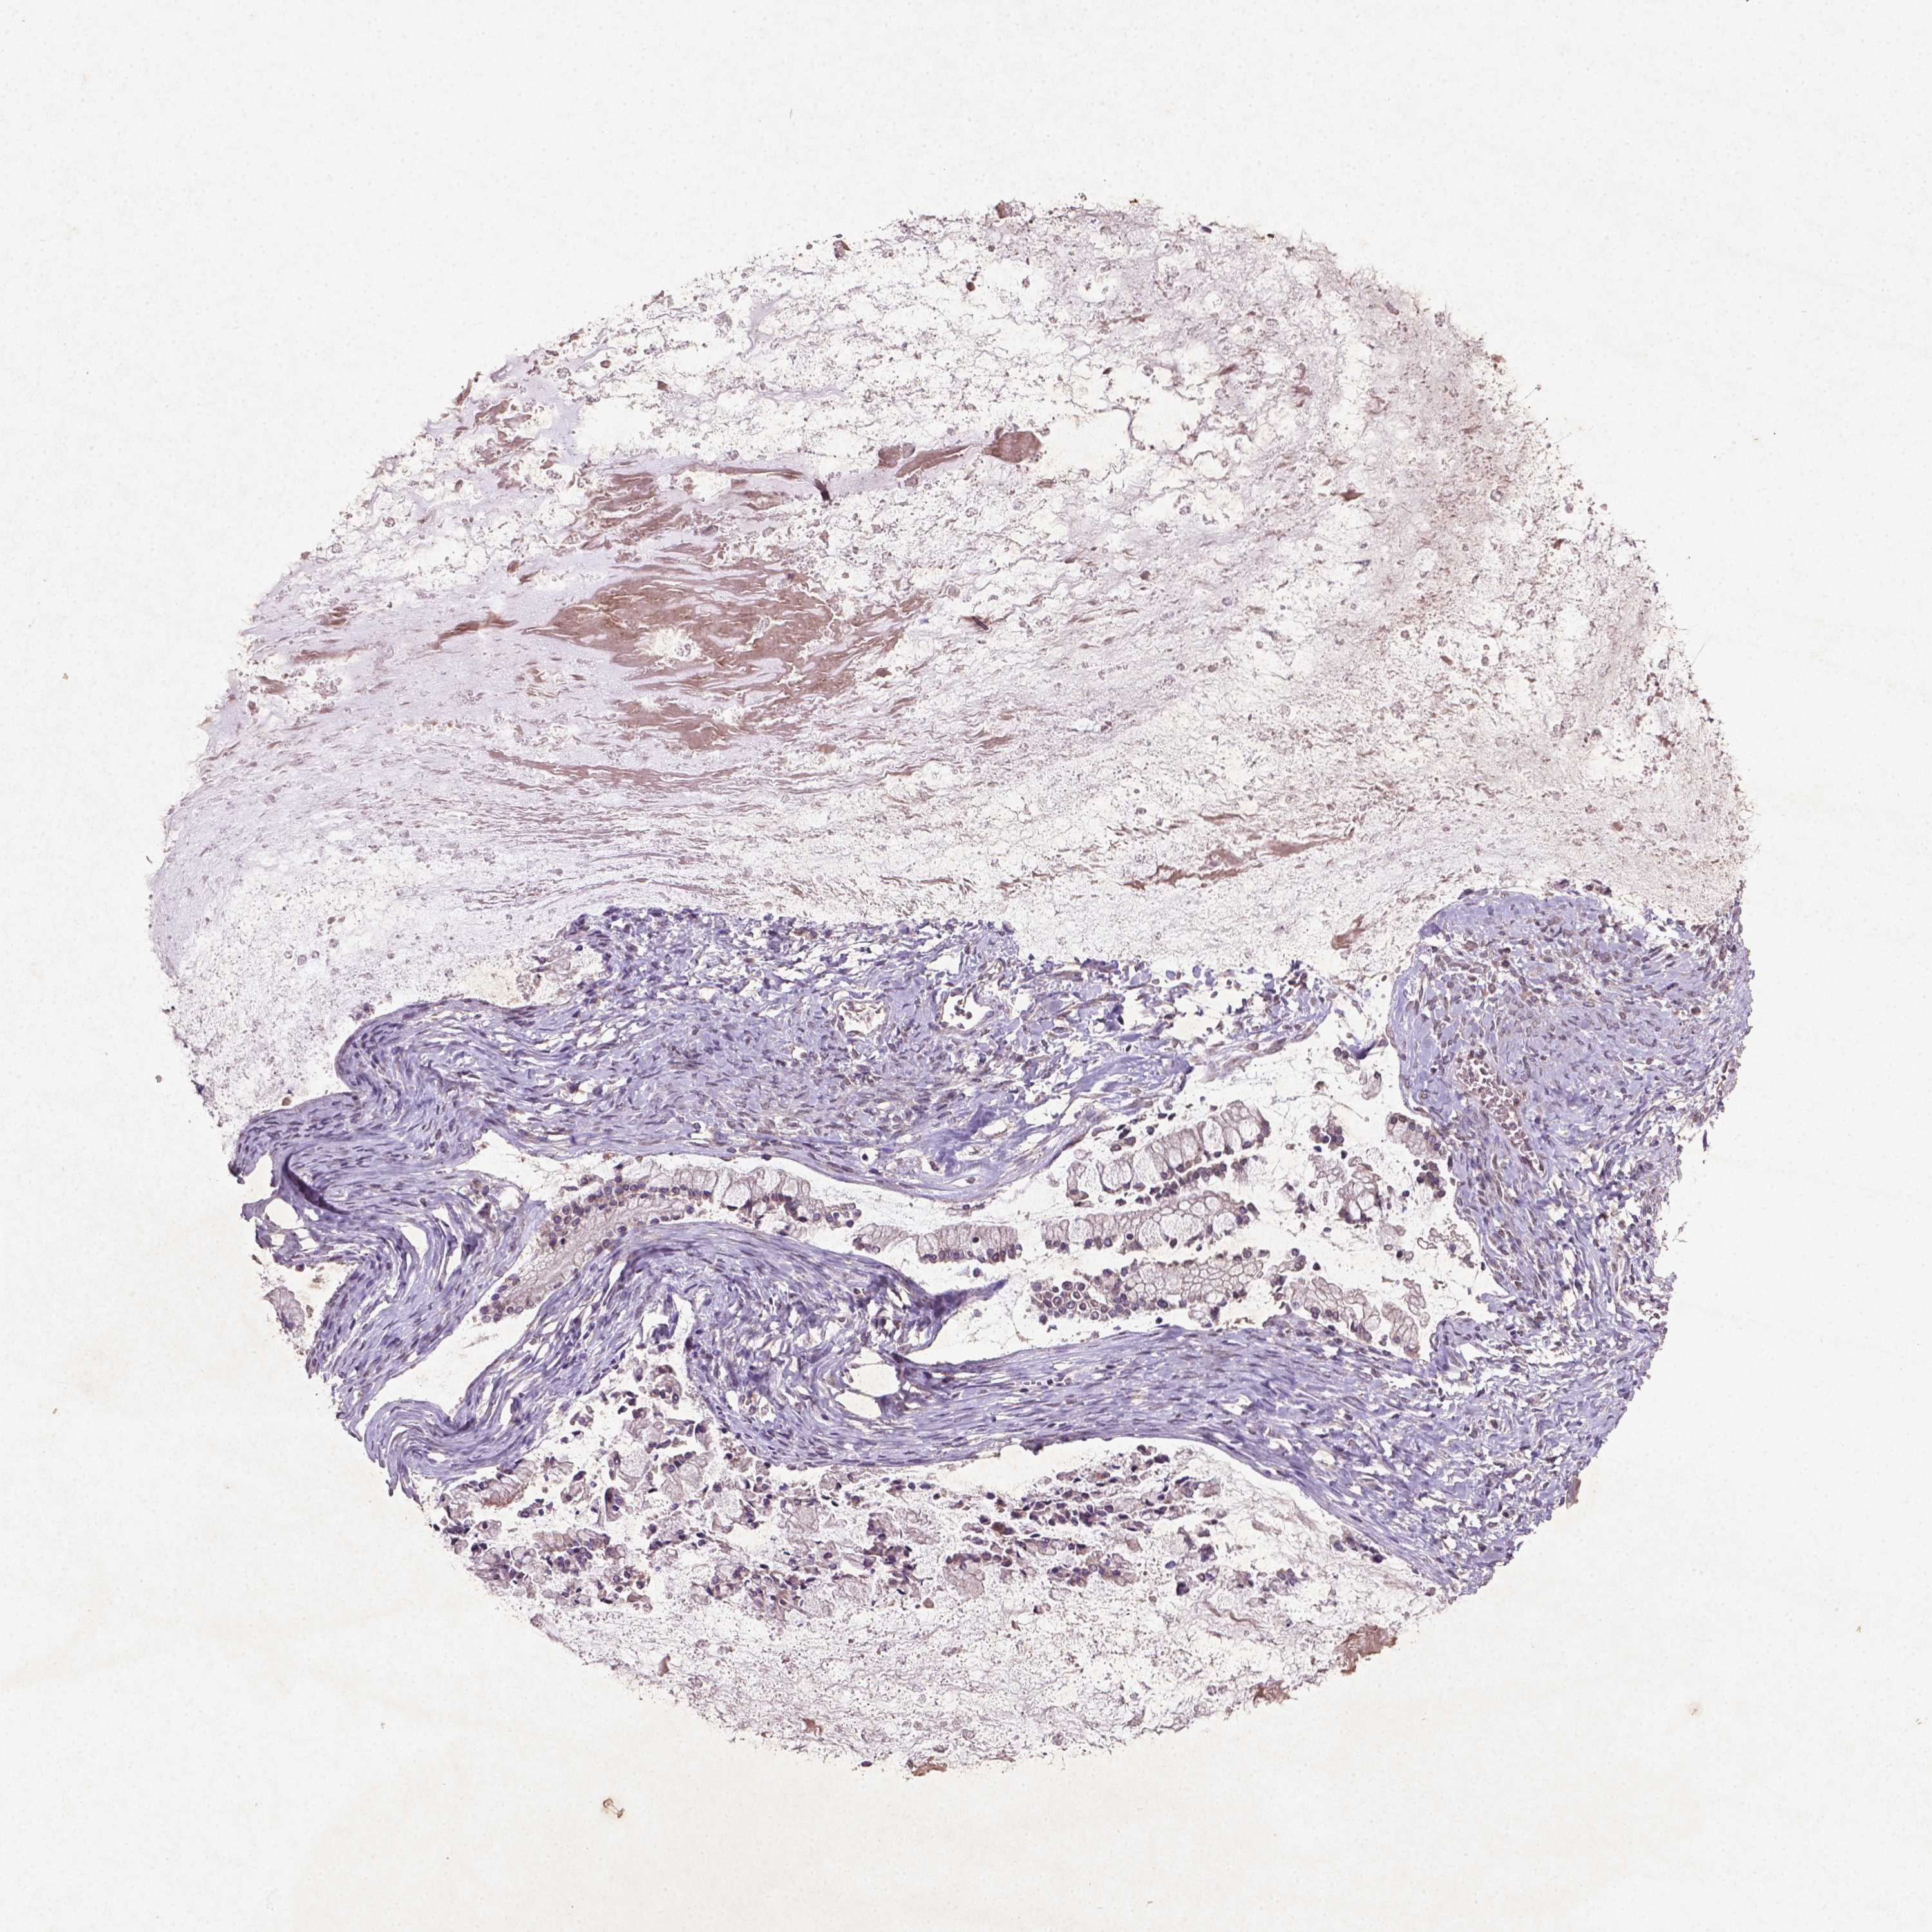

OVARIAN CANCER - Protein expressioni

A mouse-over function shows sample information and annotation data. Click on an image to view it in a full screen mode. Samples can be filtered based on level of antibody staining by selecting one or several of the following categories: high, medium, low and not detected. The assay and annotation is described here.

Note that samples used for immunohistochemistry by the Human Protein Atlas do not correspond to samples in the TCGA dataset.

Antibody stainingi

Antibody staining in the annotated cell types in the current human tissue is reported as not detected, low, medium, or high, based on conventional immunohistochemistry profiling in selected tissues. This score is based on the combination of the staining intensity and fraction of stained cells.

Each image is clickable and will lead to virtual microscopy that enables deeper exploration of all samples and also displays staining intensity scores, fraction scores and subcellular localization as well as patient and tissue information for each sample.

Cystadenocarcinoma, serous, NOS